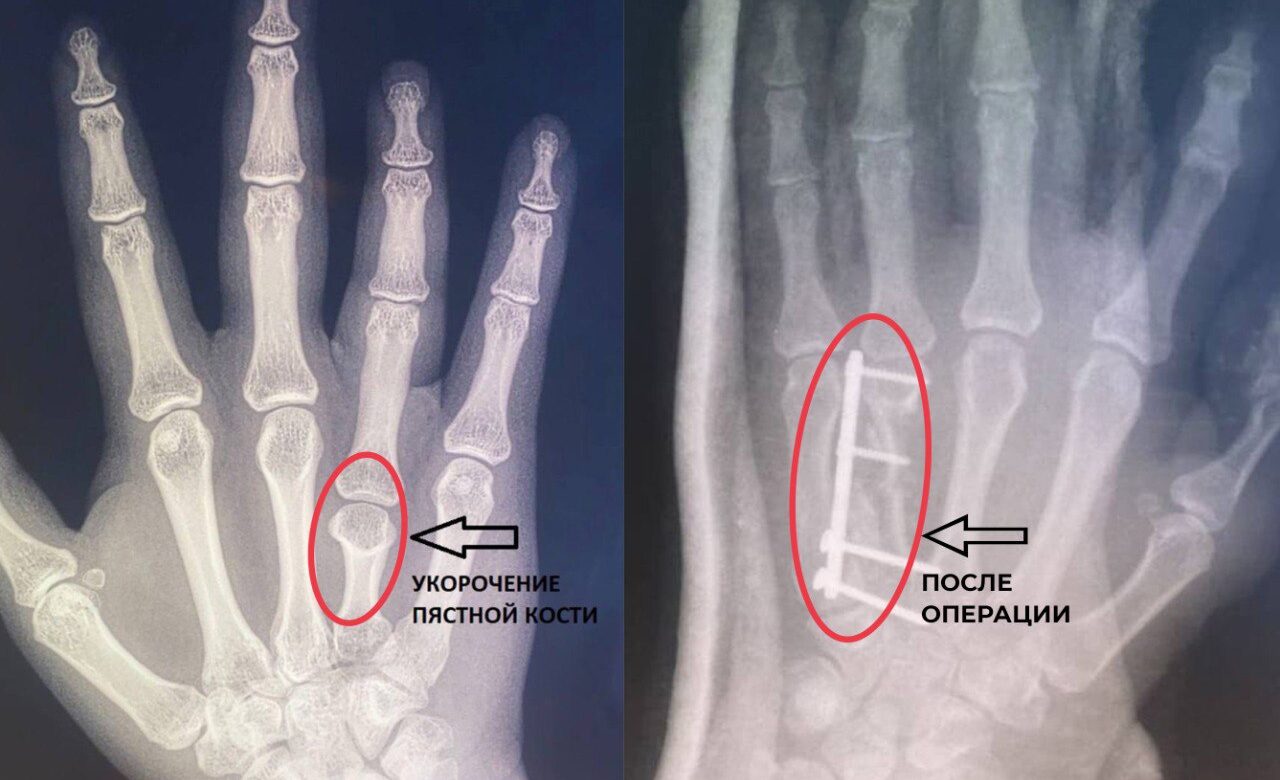

Во Владимире врачи удлинили девушке безымянный палец

Владимирские врачи из областного центра спецмедпомощи сделали жизнь одной девушки проще, удлиннив ей безымянный палец на правой руке.

У пациентки выявили брахиметакарпию – врожденная патология, проявляется укорочением одной или нескольких пястных костей, из-за уменьшается длина пальцев. Дефект опаснее, чем кажется, ведь он становится причиной проблем с мелкой моторикой. Чаше от заболевания страдают девочки.